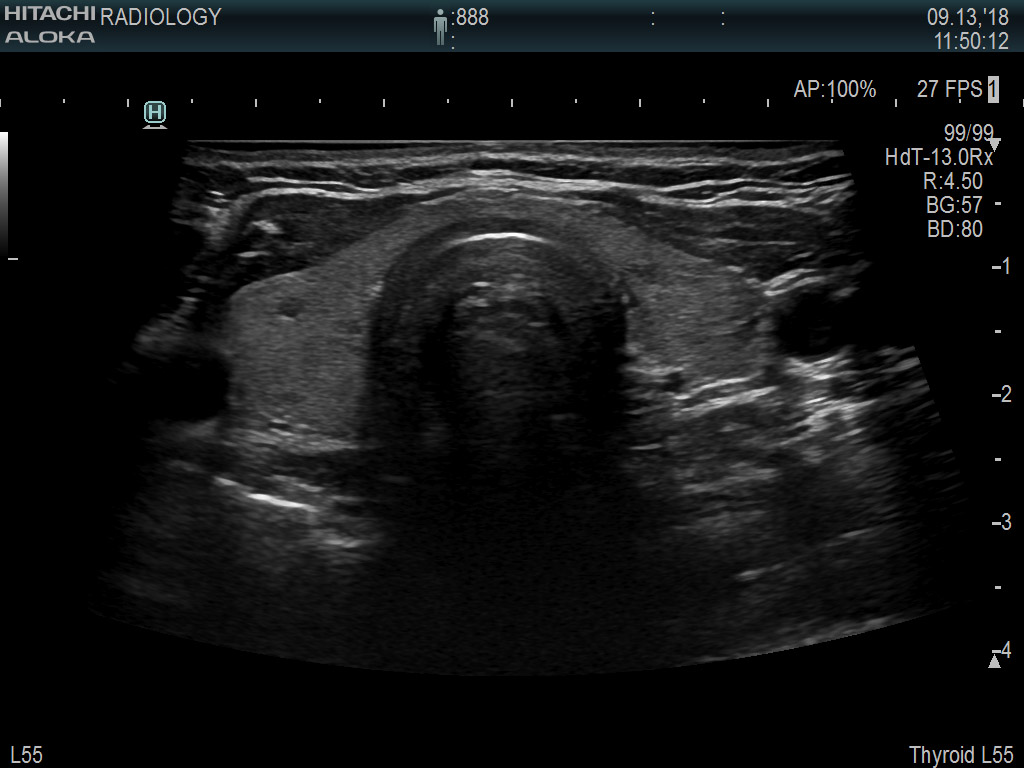

Superior guidance for all applications

Fujifilm Healthcare Americas is committed to designing tools that help surgeons navigate inside the human body and provide the necessary information to immediately make critical surgical decisions.

Fujifilm Healthcare's dedication to Surgeons provides outstanding ultrasound technology, professional support and the specialized tools necessary to best perform comprehensive real-time ultrasound imaging in Breast Surgery, General Surgery, Laparoscopic Surgery, Neurosurgery, Robotic Surgery and Surgical Oncology.